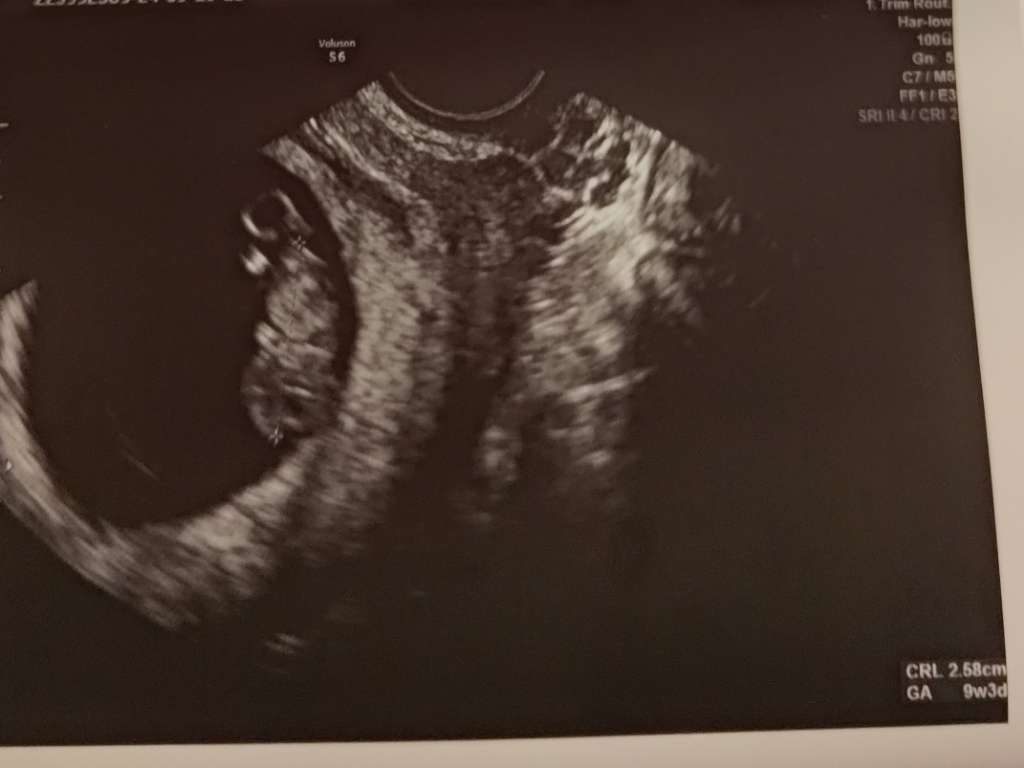

@Tinulka @KolorowaCzerń wspaniałe wieści dziewczyny. Sama się nie mogę doczekać swojej piątkowej wizyty